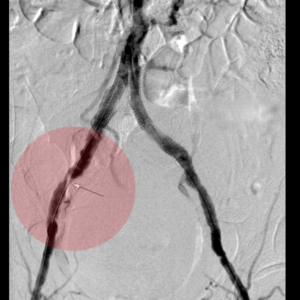

3. Stentimplantation – Einsetzen eines Stentes/ Gefäßstütze

Nach der Gefäßweitung kann durch Einrisse in den inneren Ablagerungen oder durch die Elastizität der Gefäßwand die Weitung nur ungenügend erfolgreich sein. Zur Stabilisierung des Befundes wird dann in diese Gefäßregion ein Stent eingesetzt. Dieser besteht aus einem feinen starren oder flexiblen Edelmetallgeflecht und kann auch mit Medikamenten gegen die Arteriosklerose oder zur Verhinderung der Bildung von Blutgerinnseln beschichtet sein.

Unter bestimmten Bedingungen, v.a. bei Verletzungen der Gefäße mit daraus resultierender Blutung oder lokalen Gefäßerweiterungen, werden Stents mit einer Ummantelung eingesetzt, die die Gefäßwand abdichten oder die Erweiterung überbrücken.